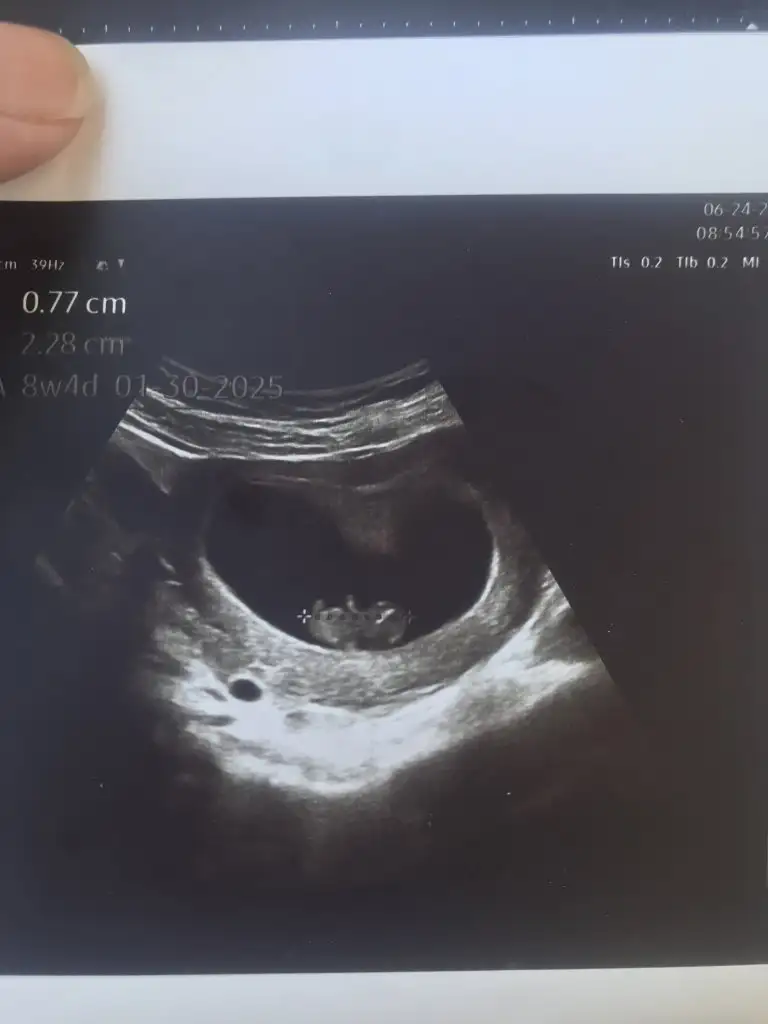

Azıcık anlıyorsam kız gibi geldi banaKızlar cinsiyet tahmini alabilir miyimbu arada 12 haftalık olduk

Yaaa maşallahKızlar cinsiyet tahmini alabilir miyimbu arada 12 haftalık olduk